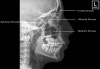

4. Adult Skull - Lateral View